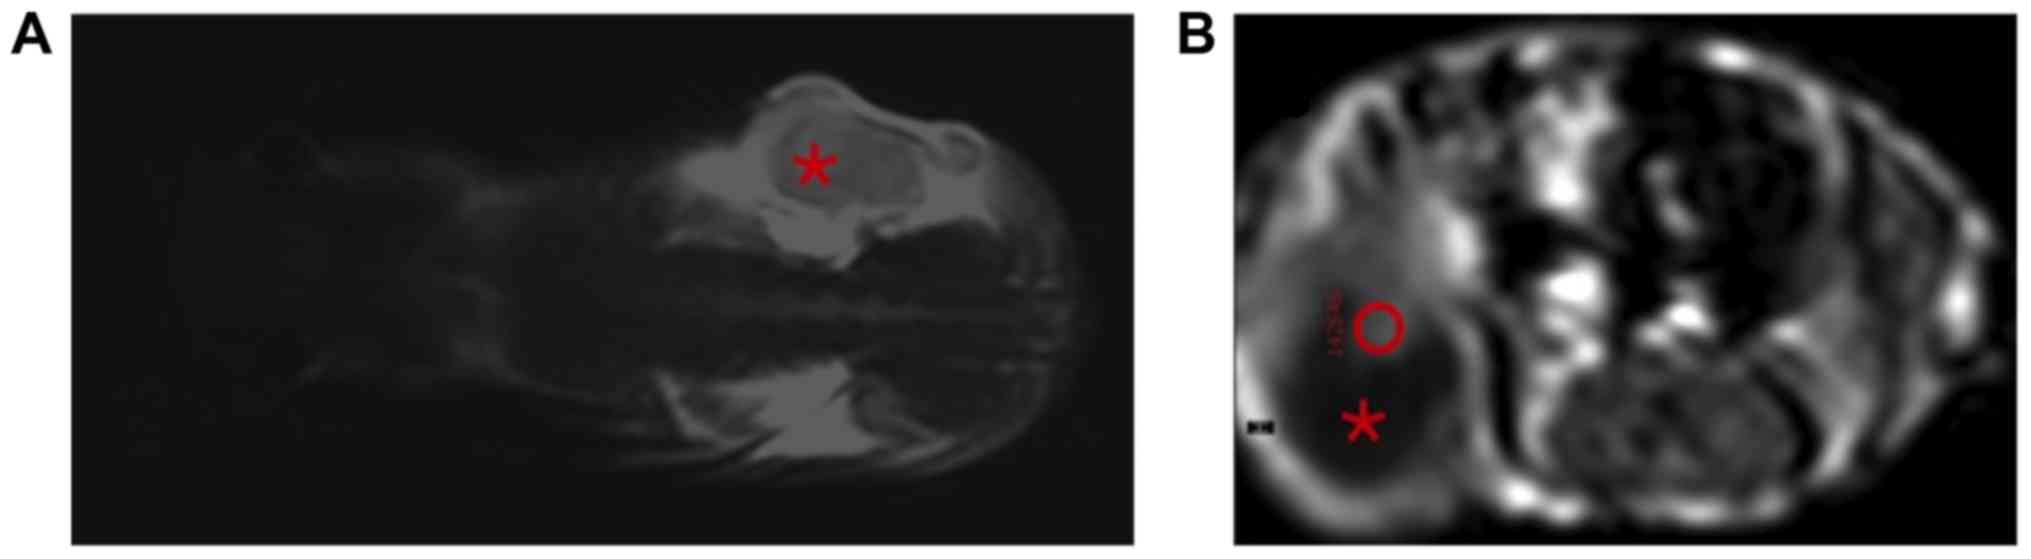

First, a T2-weighted turbo spin echo (TSE) sequence was acquired in coronal sections for the purpose of anatomical orientation (Fig. 1A). Subsequently, a dynamic T1-weighted turbo field echo (TFE) sequence was conducted in transversal sections (TE: 2.3 msec; TR: 10 msec; NSA: 1; slice thickness: 2 mm; slice gap: 0.4 mm; flip angle: 15°; dynamic phases: 250; dynamic phase time: 7.3 s, resulting in a total scan time of 30:25 min). The T1w TFE sequence included preparation pulses for signal stabilization, which had not been displayed for data analysis.

Figure 1.

(A) MR sequence for anatomical orientation. T2-weighted, coronally orientated MR image; the tumour in the right flank of the mouse is designated with the asterisk. (B) ROI placement for real-time dynamic gadofosveset-enhanced-MRI analysis. Contrast-enhanced, T1-weighted, axially orientated MR image. The tumour can be seen in the right flank of the mouse (roundish structure in the bottom left-hand corner of the image). A part of the tumour appeared necrotic, i.e., hypointense and non-enhancing in this sequence (asterisk). A ROI has been placed manually into the contrast-enhancing viable part of the tumour (red circle within the hyperintense area). MRI, magnetic resonance imaging; ROI, region of interest.

Analysis of the contrast agent dynamics

Once the acquisition of the MR sequences was completed, the tumour perfusion was analysed by using the software implemented on the MR scanner (IntelliSpace; Philips Healthcare). First of all, the particular slice was chosen, in which the contrast enhancement of the tumour was the most intensive representing an index region of viable tumour tissue with noticeable angiogenesis. In most cases, only a small part of the tumours showed an enhancement, while the major part of the tumours was non-enhancing and necrotic. This is caused by the rapid growth of U87 tumour cells that results in an occasionally inhomogeneous tumour texture. Then, a region of interest (ROI) was placed manually within the contrast-enhancing part of the tumour (exemplarily demonstrated in Fig. 1B). This approach is based on the subjective, individual decision of the investigator, but as mentioned above, it seems to be the best strategy concerning these inhomogeneous tumours in these small animals.